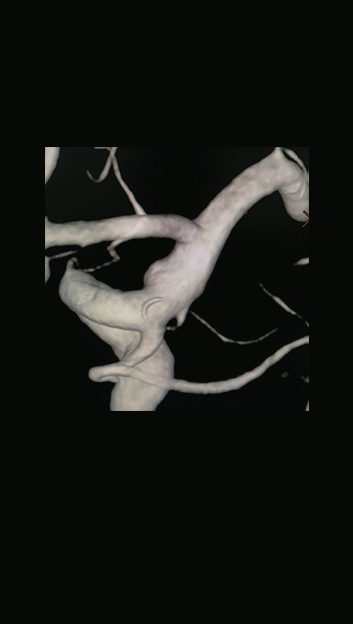

Echelon微导管塑形,瘤颈口到位

1.2)

Navien + Phenom助力上高到颈内动脉末端

3.1)

回撤到平直段,半释放pipeline

Navien继续上高,推支架,确保瘤颈处支架的贴壁